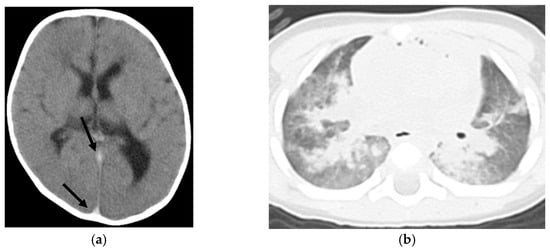

Supplementary Tables S1 and S2 present clinical information and CT findings of the non-ROSC (Figure 1) and ROSC groups (Figure 2), respectively. The non-ROSC group showed significantly higher incidences of several findings compared to the ROSC group, including brain swelling (84% vs. 12.5%; p < 0.001), loss of cerebral gray-white matter differentiation (74% vs. 37.5%; p = 0.033), symmetrical consolidation/ground-glass opacity (95% vs. 50%; p = 0.017), cardiomegaly (84% vs. 25%; p = 0.006), hyperdense aortic wall (84% vs. 0%; p < 0.001), narrowed aorta (100% vs. 0%; p < 0.001), gas in the mediastinum (80% vs. 0%; p < 0.001), and hepatomegaly (79% vs. 12.5%; p = 0.002). Neither pericardial effusion nor subcutaneous fatty edema was observed in any case. There were no significant differences between the non-ROSC and ROSC groups in the incidence of loss of cerebral gray-white matter differentiation, hyperdense intracranial venous sinus, symmetrical/asymmetrical consolidation/ground-glass lung opacity, cardiomegaly, hepatomegaly, dilated inferior vena cava, dilated gastrointestinal tract, or gas in the upper abdominal organs. A summary of the differences in the WBCT findings between the non-ROSC and ROSC groups is provided in Table 2.

Figure 1.

Nine-month-old boy with non-ROSC (case No. 19 in Table S1). (a) Observations in the head included brain swelling, loss of cerebral gray-white matter differentiation, and hyperdense intracranial venous sinus (arrows). (b) Symmetrical consolidation/ground-glass opacity of the lungs was noted. (c) In the mediastinum, findings included cardiomegaly, a hyperdense aortic wall (arrows), and gas in the cardiac cavity (arrowheads). (d) A narrowed aorta (arrow) and hepatomegaly were observed.